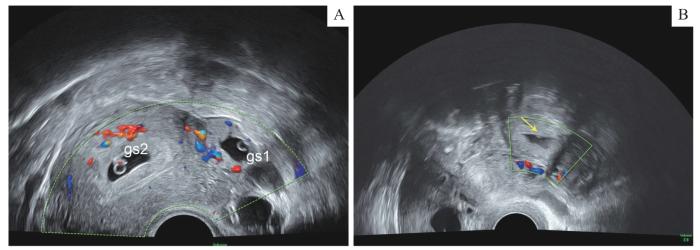

超声检查THP 代表图像

Note :A. Type Ⅰ (type of gestational sac). B. Type Ⅱ (type of mixed echo). The arrow indicates mixed mass of fallopian tube. gs1—gestational sac in uterus; gs2—gestational sac in fallopian tube.

Representative ultrasound images of THP

... 参考LI等[6 ] 的诊断标准,对疑似THP异位超声图像进行判断.其可分为2种类型:Ⅰ型为孕囊型,超声图像显示在输卵管部见孕囊,即无回声包块内见卵黄囊或见胚芽及心管搏动;Ⅱ型为混合型,超声图像显示在输卵管部存在除孕囊外的低回声及混合回声包块.如诊断为疑似THP,则收入住院,并作后续诊断或治疗.对接受辅助生殖的孕妇一般在其接受辅助生殖后14 d检测血HCG水平;若血HCG水平大于10 U/L,再在孕6~8周进行超声检查[11 ] .参考该方法,本院常规为接受辅助生殖14 d后的孕妇检测血HCG水平;对于血HCG水平大于10 U/L者,在孕39 d时复查血HCG水平.复查时,若发现伴有腹痛、阴道流血等不适症状,当日再行超声检查;无不适者,则常规在孕46 d及之后进行超声检查.依据这2个时间点,本研究将孕妇按接受超声检查的孕龄分为3组:①孕≤38 d组.②孕39~45 d组.③孕46~73 d组. ...